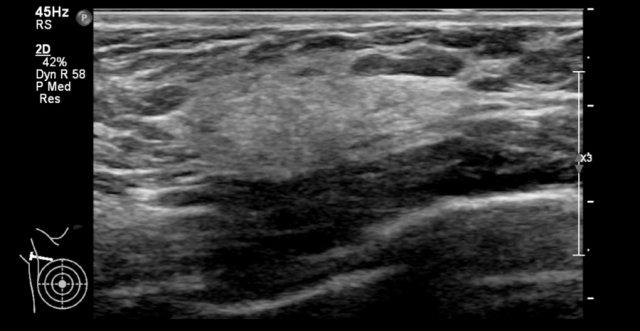

Mô xơ tuyến đôi khi phát triển rất dày đặc đến mức chùm tia siêu âm khó có thể xuyên qua được.

Điều này có thể tạo ra hình ảnh giả của một khối giảm âm bờ không đều kèm bóng cản phía sau, dễ nhầm lẫn với ung thư biểu mô (xem video).

Tuy nhiên, khi thực hiện động tác ép nhẹ lên vùng mô này, có thể thấy đây chỉ là mô xơ tuyến tăng âm phát triển rõ rệt.

Thông thường, đây là những bệnh nhân trẻ tuổi đến khám vì khối lớn, đau ở vú.